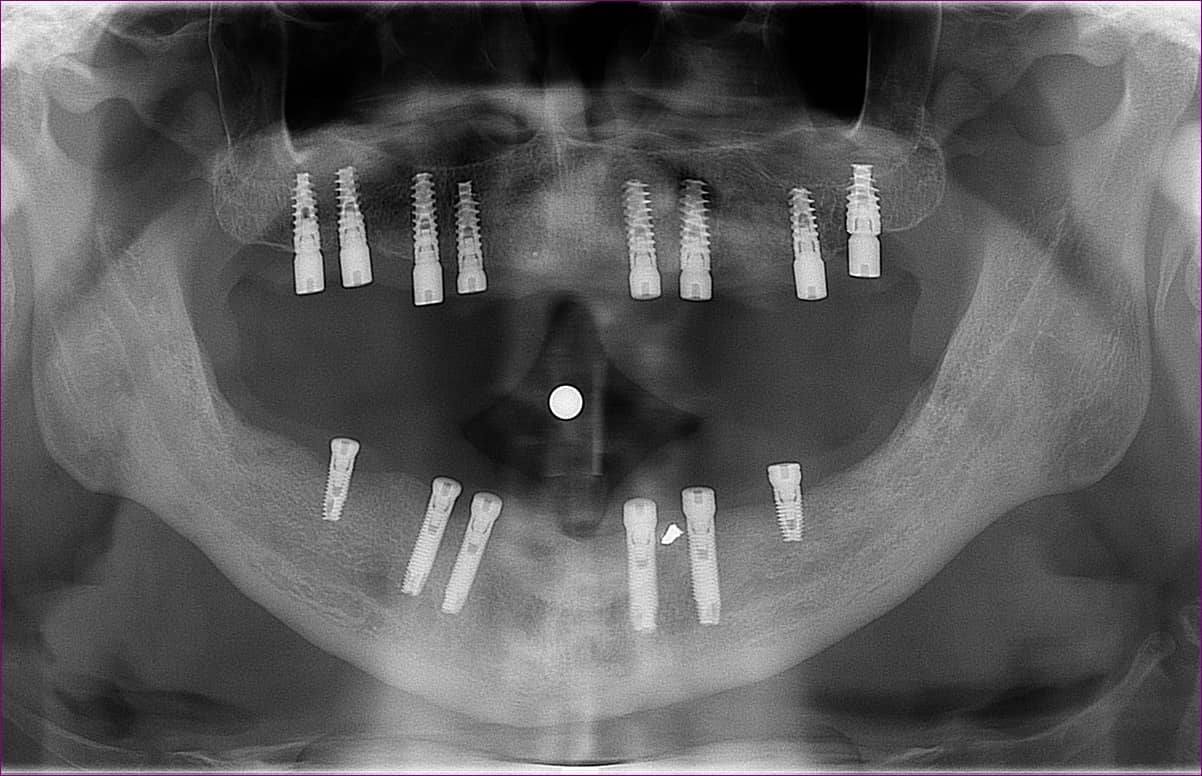

Kezelését dr. Záhonyi Balázs kollégánk végezte. A páciensnek felül 8, alul 6 implantátum került előzőleg beültetésre, az implantátumokba pedig ún. gyógyulási csavarokat helyeztek.

Ideiglenes megoldásként felső és alsó teljes kivehető fogpótlást viselt az átmeneti időszakban.